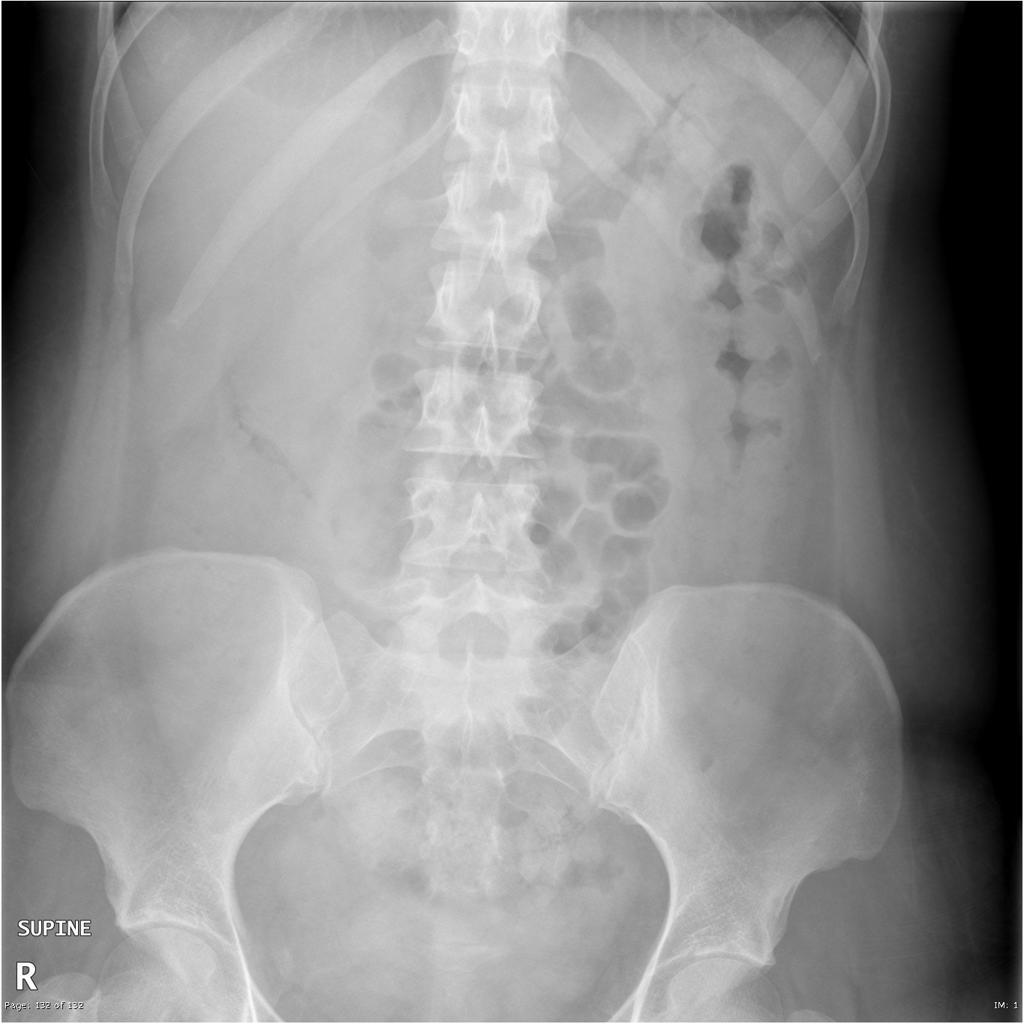

What is the following?

Thumb print sign - a radiographic sign of large bowel wall thickening, usually caused by oedema, related to an infective or inflammatory process (colitis). It can be seen in ischaemic colitis